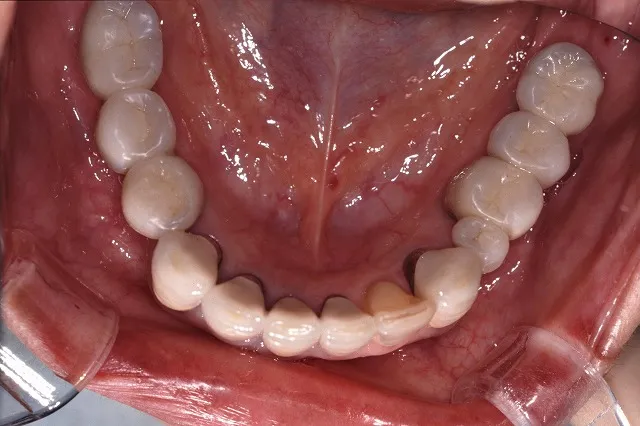

治療後

■治療後